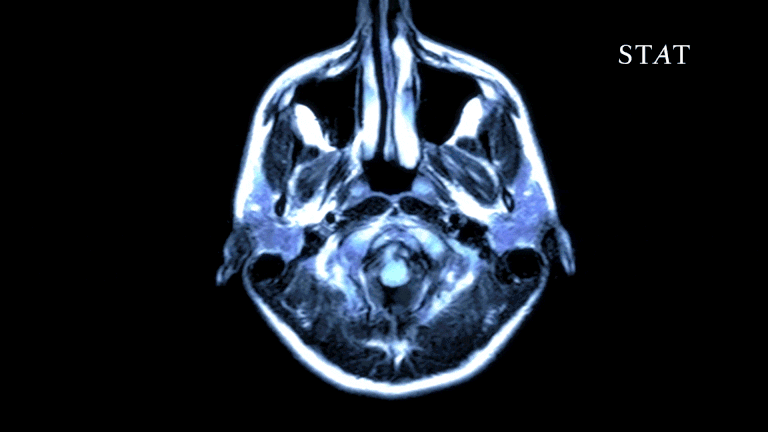

表现大脑不同区域神经元活动的更为精细的图像就是人脑的核磁共振图像(MRI)。功能性核磁共振成像(functional magnetic resonance imaging, fMRI)是一类基于核磁共振(MRI)的成像方法,用于显示脑不同区域代谢活动随时间的变化(图5所示)。脑代谢变化一般是脑活动变化引起的,如果大脑的认知状态发生改变(如大脑开始思考某个问题或进行某种活动或大脑中不受意识调节的某个潜意识过程发生变化),fMRI就可以采集到这种变化所引起的脑活动图像。fMRI基于核磁共振成像原理,而MRI是使用核磁共振回旋波在磁场梯度中创建对比度(回旋波的不同)来成像的,这些图像可以包含许多不同类型的对比度(不同),如T1加权、T2加权、磁化率、流量等。而fMRI就是利用这些不同类型的对比度信息来研究脑活动变化的一种成像技术,其主要的一种形式是通过与脑活动代谢有关的血氧浓度水平(Blood Oxygen Level Dependent, BOLD)来研究脑活动。脑血氧水平依赖(BOLD)的功能磁共振成像(fMRI)技术可以实时跟踪大脑特定活动诱导或自发神经代谢调节导致的脱氧血红蛋白浓度的变化过程,以此研究脑部的神经元活动。

图5 大脑活动核磁共振动态图像(来自STAT网络)

大脑中所有神经信号的传导过程,包括动作电位的产生和传播、囊泡与前突触结的结合、神经递质通过突触间隙的释放、动作电位在突触后结构中的接收和再生、多余神经递质的清除等活动,都需要耗费三磷酸腺苷(ATP)所提供的能量。ATP主要由线粒体通过葡萄糖的糖酵解氧化产生,这个过程会产生二氧化碳代谢物。当大脑的某区域(开始处于静息状态)被人体某种活动(如敲击手指或听音乐)激活时,额外的神经放电和相关信号的增加会导致局部能量需求增加,进而受影响区域的脑氧代谢率(cerebral metabolic rate of oxygen, CMRO2)上升。由于毛细血管附近组织中局部储存的氧气被糖酵解短暂消耗,废物堆积,各种化学代谢产物(如CO2, NO, H+)会刺激毛细血管上游动脉括约肌舒张而引起血管网扩张,从而增加局部毛细血管的血流量,借以恢复局部的血氧水平来补充氧气的消耗;然而增加的血流量输送过来的氧气大于脑代谢所消耗的氧气量导致毛细血管中有氧血红蛋白(hemoglobin O2, HBO2)浓度大大增加。所以在某个脑活动事件中,大脑的认知活动导致耗氧增加,血管内外脱氧血红蛋白(HB)增加而有氧血红蛋白(HBO2)快速减少,之后在一到两秒的时间内代谢产物会刺激毛细血管扩张导致血流增加,毛细血管内有氧血红蛋白浓度将高于脱氧血红蛋白,这一变化过程即为某个神经事件的血流动力学反应。这个血流动力学反应过程可以被MRI所记录,这是因为HB作为内源性造影剂为顺磁性,MRI信号弱,其在毛细血管静脉侧被抑制(深色),而在脑活动激发状态下,血流量增加导致HB减小而HBO2增加,此时MRI信号增强(亮色),此即为血氧水平BOLD信号增强,这一强弱变化的过程就如图5所示。

通过fMRI图像,科学家对做梦过程中大脑的代谢活动进行了研究,发现了著名的“洗脑”现象,在梦中血流量会如涨潮一样出入大脑,而此时脑脊液也会随血流的退潮而周期进入大脑。这种清洗大脑的过程是在大脑很多区域的活动被抑制的情况下发生的,在做梦的浅睡阶段,大脑在白天活动强烈的区域因为需要更多地“清洗”,该区域的神经元会被触发而放电,从而导致了视觉、听觉等知觉的反应而产生梦境,而该区域神经元的血氧代谢活动就能被该区域的fMRI图像所记录。